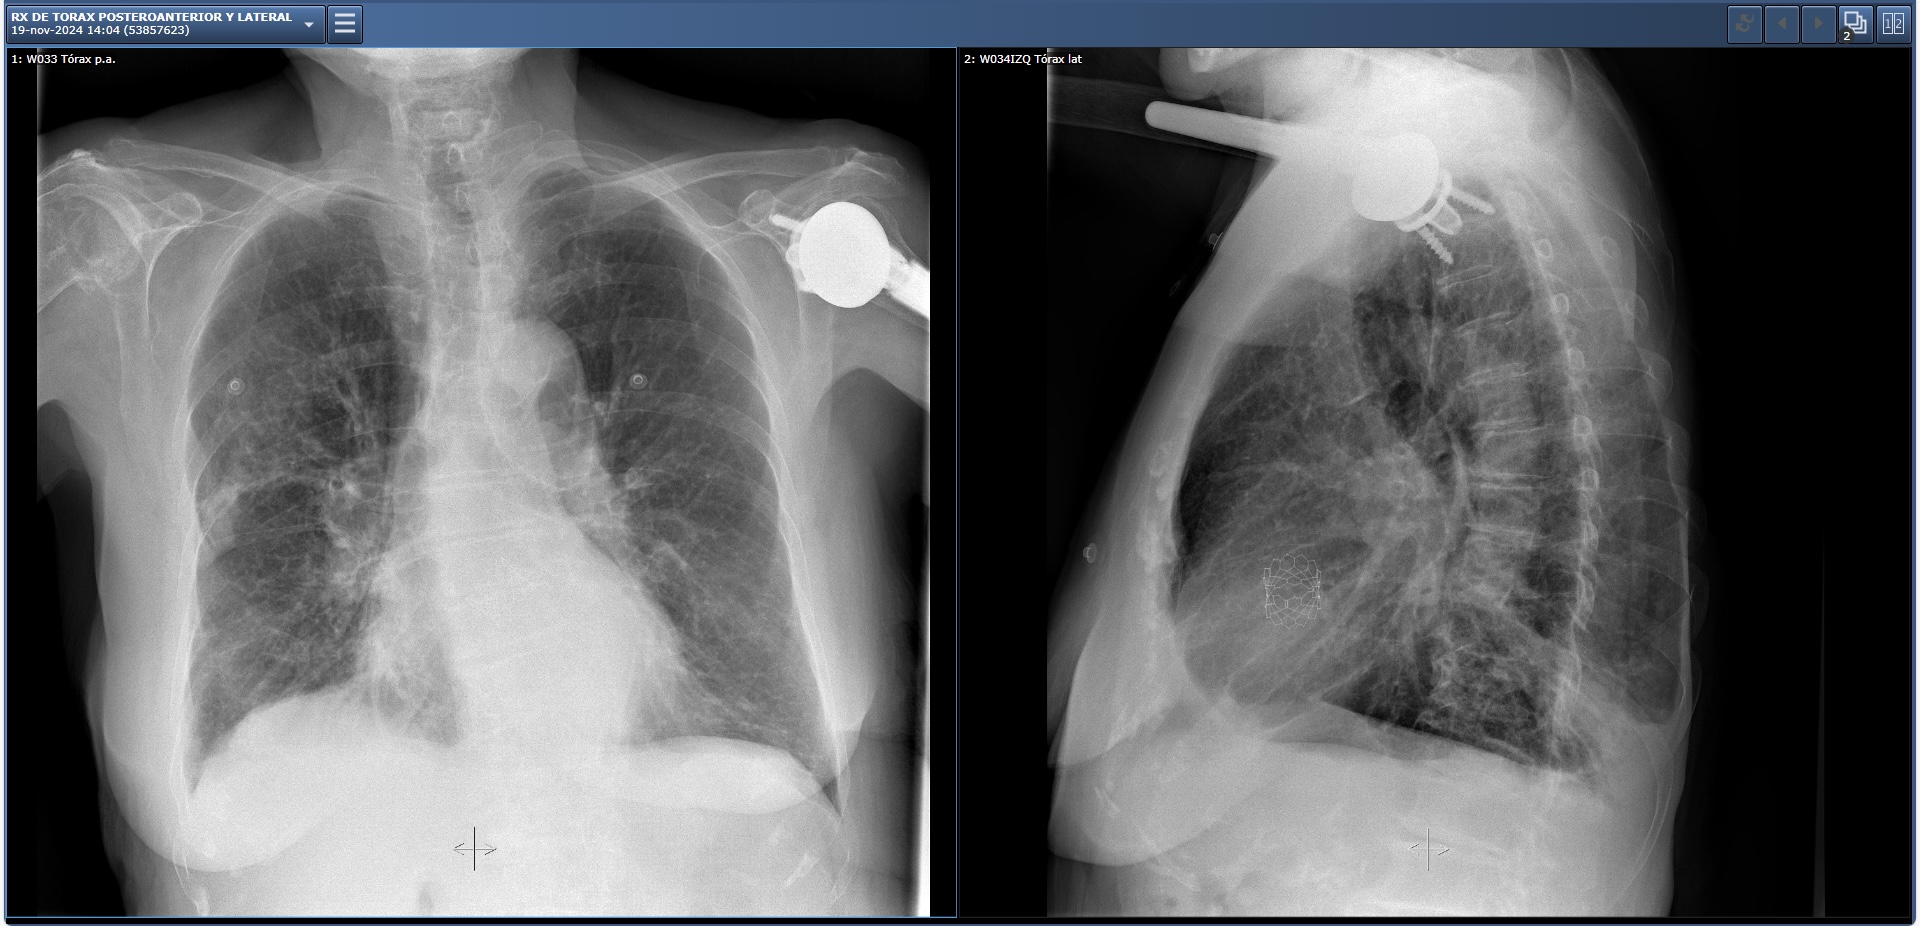

Mujer de 86 años que acude a Urgencias por tos y expectoración grisácea de 4 días de evolución. Sensación distérmica. No dolor torácico. Disnea de esfuerzos moderados. No ortopnea ni DPN ni aumento de edema. Diarrea sin dolor abdominal. No clínica urinaria. No otra clínica asociada.

*Ctes: PA: 119/74 mmHg, FC: 100 lpm, Temp: 35,6 ºC, SatO2: 93% (FiO2 21%).

Tórax. AC: arrítmica, sin soplos. AP: roncus bilaterales móviles con la tos. Sibilancias bilaterales difusas.

Pruebas complementarias:

Diagnóstico diferencial: Broncoespasmo por reagudización asmática, infección de la vía respiratoria alta y baja e insuficiencia cardíaca aguda.